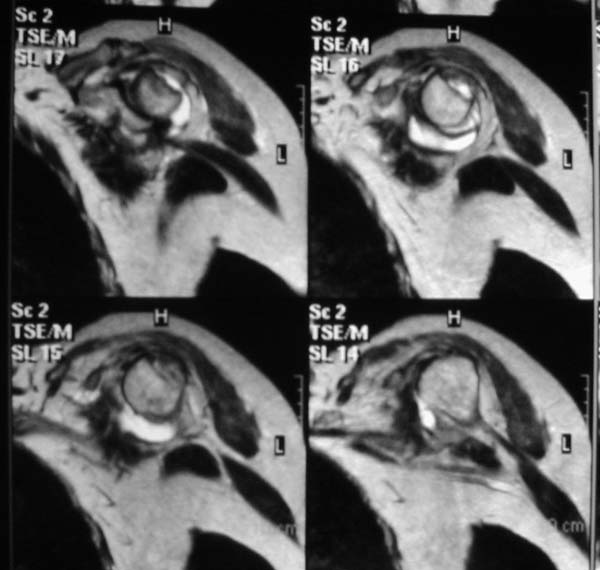

Re: Вывих плеча

> Непонятный очаг по заднему контуру

> Именно этот участок и смущает больше всего.

"Прицельная" съемка малопонятного очага.

В приложенном файле - МРТ изображение. Более информативно, чем предыдущий вариант? менее? или также?